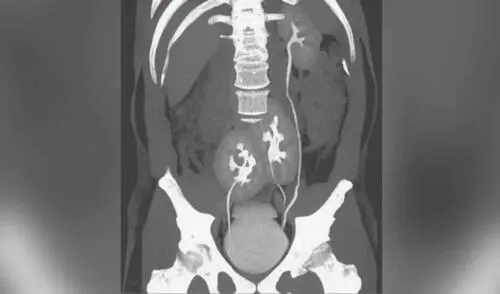

Este fue el caso de un hombre de 38 años en Brasil que, en 2020, fue al médico por un dolor lumbar. Sin embargo, tras una tomografía computarizada, él descubrió que tenía esta extraña condición.

El tercer órgano se encontraba fusionado con el riñón del extremo derecho, cerca de la pelvis, indicó un artículo de la revista The New England Journal of Medicine (NEJM).

En el caso del hombre brasileño, el dolor de espalda no se debía a tener más riñones, sino a un disco herniado, una afección relativamente común en los amortiguadores cartilaginosos que sostienen la espina dorsal.